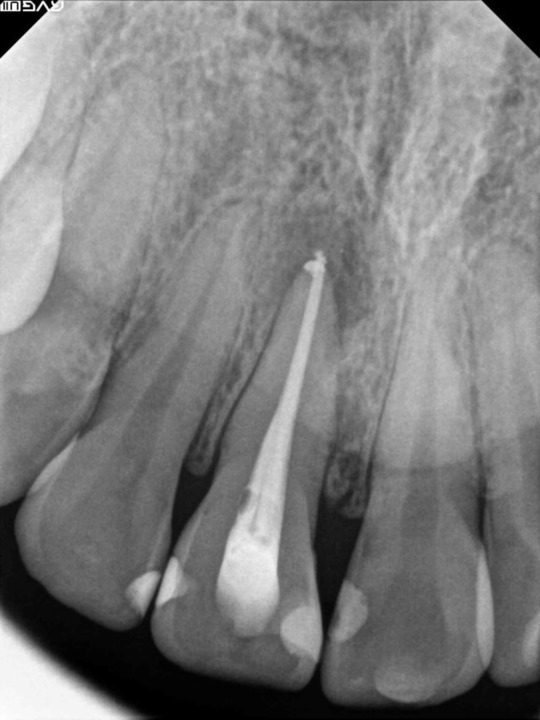

症例3

フィステル(瘻孔)があって、変色している症例。根管治療をすると、フィステルは消失。

レントゲン写真がこちら。根管治療&根管充填(この場合キャナルス&ガッターパーチャ)後。

で、漂泊してCR充填すればきれいに出来上がり。